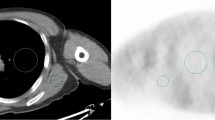

In a first step, all data were automatically analysed using Matlab (MathWorks, Natick, MA, USA) to estimate the NECR versus activity concentration in a similar manner to the National Electrical Manufacturers Association (NEMA) analysis and based on previous publications [8]-[12]. This measurement is essentially the same usually performed on phantom data, but the required data (the number of true, scattered and random counts) are estimations either provided by the scanner software or automatically extracted from the reconstructed image. To determine the NECR for a bed position of patient data, the following steps were used: the PET raw data files were used to measure prompts and to calculate randoms from singles and obtain the bed position duration. Then, the reconstructed PET images were used to obtain an estimate of the model-based scatter fraction. With those two items, the NECR was calculated for each bed position, and the patient NECR was an average of all whole-body bed positions. By using the PET images, voxels above a fixed activity concentration of 1.0 kBq/mL, the average activity concentration for all voxels in the bed position was calculated. Decay to each bed position based upon its start time relative to scan start was applied as well.

IQL showed moderate but statistically significant correlation with NECR (r = 0.64 and r = 0.67, respectively, p value <0.01) (see Figure 1). The mathematical functions for which correlate IQL and NECR for the entire data and for each BMI group (from I to IV) of patients are as follows: y = 0.0106x + 0.9734, y = 0.0049x + 1.8259, y = 0.0045x + 1.7194, y = 0.0056x + 1.4105 and y = 0.0197x + 0.1126.